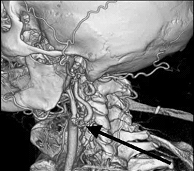

Ангиография – это наиболее точный метод, позволяющий увидеть на экране рентгеновской установки то, что происходит внутри сосуда (рис. 4). С него начинают, если пациент уже перенес инсульт и по данным УЗДГ МАГ выявлены значимо ограничивающие кровоток сужения сосуда, то есть высок риск повторения инсульта. Исследование проводится в специальной операционной, оснащенной ангиографической установкой.

Рис. 4. Критические стенозы внутренней сонной артерии (ангиография).

Во время ангиографии очень тонкий катетер вводится в артерию на ноге и продвигается к сосудам шеи. Место введения катетера будет обработано антисептиком и обезболено. После этого через катетер вводится контрастное вещество, делающее видимыми артерии, питающие мозг, под рентгеновскими лучами. Врач произведет съемку артерии. Если есть стенозы или окклюзии артерий – они будут обнаружены.